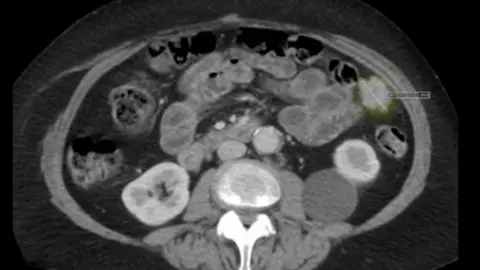

Anne Shaw, 68, who had previously been given the all-clear from the disease, underwent a routine scan on her hip in 2019 but the tumour in her ovary was missed.

She was told the tumour had been 3cm (1.1in) long on the initial scan but by the time it was detected, it had grown to four times the size.